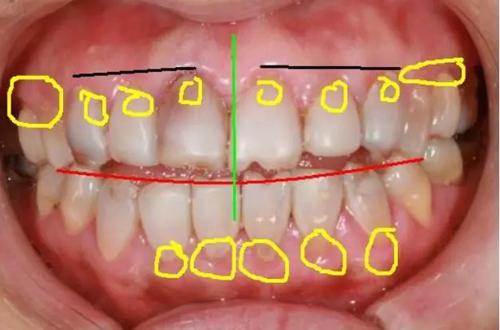

如下面圖一照片,我們?cè)诨颊咝枰淖兊牡胤椒謩e做了標(biāo)記,并進(jìn)行先期的設(shè)計(jì)。

(圖一)

1,黑線(xiàn)牙齦的高度:

患者左側(cè)牙齦高度較正常,右側(cè)13的牙齦明顯低于12,右側(cè)牙齦至少要與左側(cè)接近。

2,紅線(xiàn)切緣:

由于患者開(kāi)頜較重,縱面曲線(xiàn)已經(jīng)改變,所以在美學(xué)修復(fù)的同時(shí),應(yīng)注意牙齒生理上意義。

3,綠線(xiàn)正中線(xiàn):

正中線(xiàn)是起到一個(gè)均衡的意義,除上下頜盡可能對(duì)齊外,同時(shí)要保證必須與面中線(xiàn)一致。

4,黃線(xiàn)處牙齦:

患者的牙齦(牙周)已經(jīng)明顯紅腫,必須要在牙周穩(wěn)定后才能進(jìn)行修復(fù)。如果是原修復(fù)體的原因,建議先拆除,去除對(duì)牙齦的刺激。如果是患者自身原因,建議治療后觀察,修復(fù)治療待定。